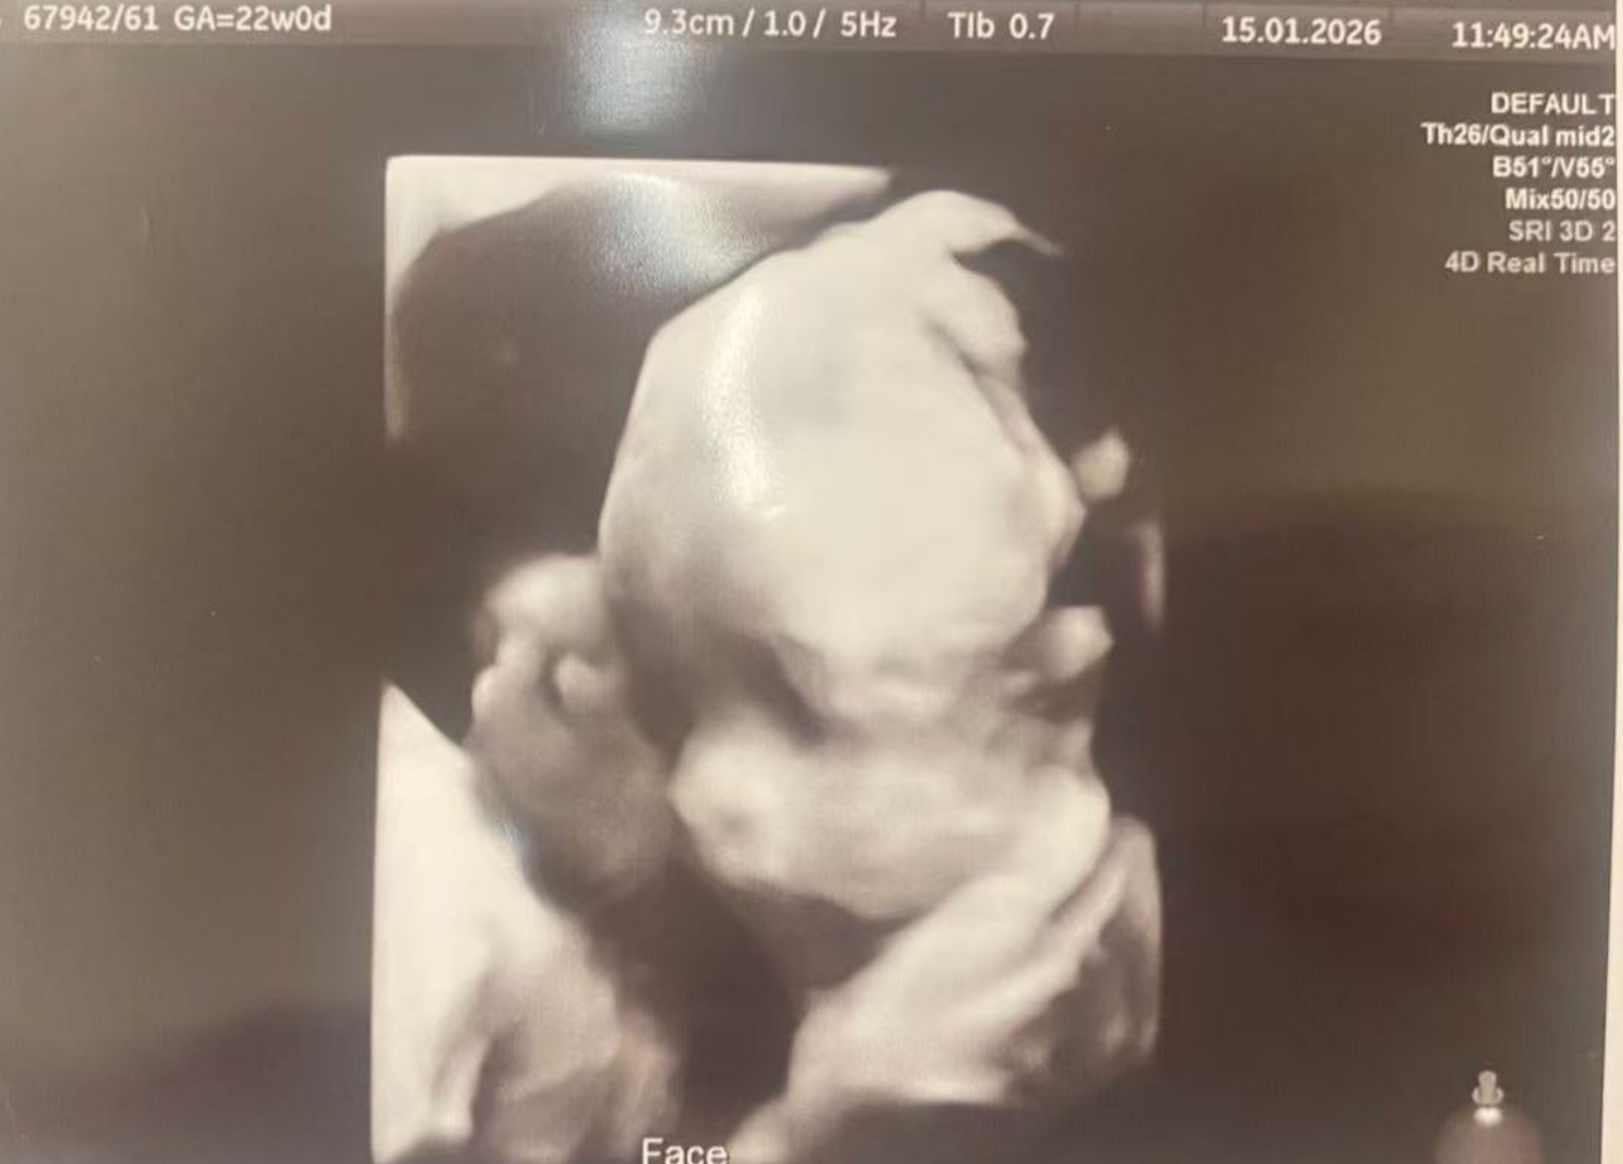

25週、すべて順調、また一人の赤ちゃんが四次元検査を無事に通過しました。すべての発育指標は健康です。これは単なる順調な産検ではなく、まるで小さな天使が世界に向けて発した最初の「健康宣言」のようです。この喜びが続き、間もなくの再会を楽しみにしています。